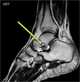

Sinus tarsi syndrome